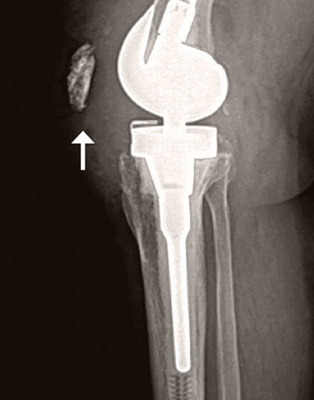

Abb. 1

Im Röntgenbild steht die Kniescheibe im Verhältnis zur Gelenklinie zu hoch. Eine Lockerung lässt sich im Röntgenbild nicht erkennen. Die Prothese liegt gut in der Achse.

In der klinischen Untersuchung stellte sich das Knie als instabil heraus. Die Kniescheibe und der seitliche Bandapparat waren zudem schmerzhaft. Im Röntgenbild (Abb. 1) zeigte sich ein etwas tiefer Sitz der Knieprothese im Verhältnis zur Kniescheibe ohne Lockerungszeichen, was nach 16 Jahren seit dem Einbau eine mögliche Ursache für die Beschwerden hätte sein können. Unter der Röntgendurchleuchtung in der Sprechstunde wurde das Knie erneut untersucht und die Instabilität des Kniegelenks sichtbar gemacht.